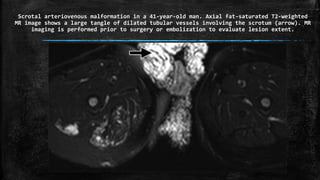

Scrotal arteriovenous malformation in a 41-year-old man. Axial fat-saturated T2-weighted

MR image shows a large tangle of dilated tubular vessels involving the scrotum (arrow). MR

imaging is performed prior to surgery or embolization to evaluate lesion extent.